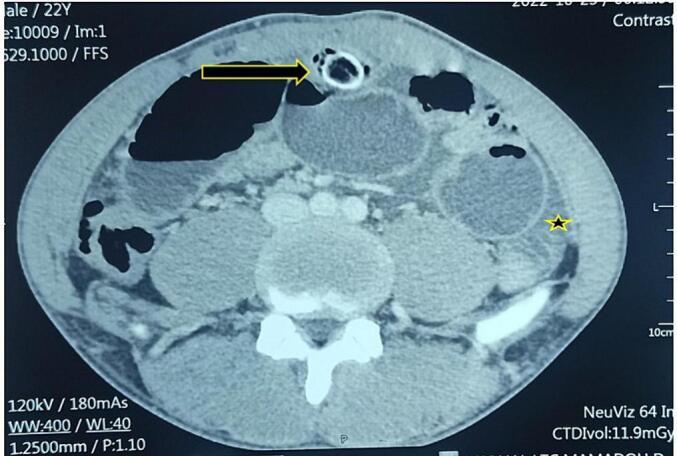

We present the case of a 22-year-old patient admitted for bowel obstruction persisting for three days and periumbilical tenderness. Abdominal CT tomography revealed a hyper dense circular structure with a diameter of 2 cm, small bowel distension of 41 mm, and free fluid. During surgical exploration, a Meckel diverticulum was found between the antimesenteric border of the small bowel and posterior wall of the umbilicus. The Meckel diverticulum was resected, and upon examination, it was found to contain a calcified phytobezoar. The postoperative course was uneventful.

我们报告一例22岁患者,因肠梗阻持续三天且脐周压痛入院。腹部CT断层扫描显示一个直径2厘米的高密度圆形结构、小肠扩张至41毫米以及游离液体。在手术探查过程中,在小肠系膜对侧缘与脐后壁之间发现一个梅克尔憩室。切除该梅克尔憩室后检查发现其中含有一个钙化植物性胃石。术后过程顺利。